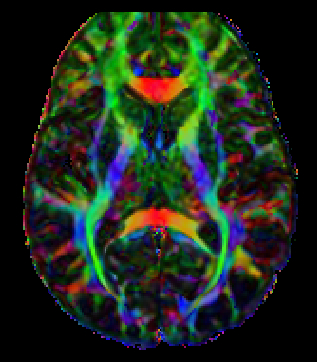

MRI, or magnetic resonance imaging, is a sophisticated medical imaging technique that captures intricate, high-resolution images of various organs and structures within the body. This advanced technology operates using powerful magnets and radio waves, which work together to create detailed visual representations displayed on a computer, allowing radiologist to assess conditions with remarkable clarity.

One of the standout advantages of MRI is its safety profile, as it does not utilize any form of ionizing radiation. This feature makes it an exceptionally safe option for even the youngest patients, including children and infants. For very small children, undergoing an MRI while they are peacefully asleep—often after being fed—can make the experience much easier. Conversely, for older children who may be unable to remain still during the procedure, intravenous sedation or General anesthesia (GA) might be necessary to ensure their comfort and safety.